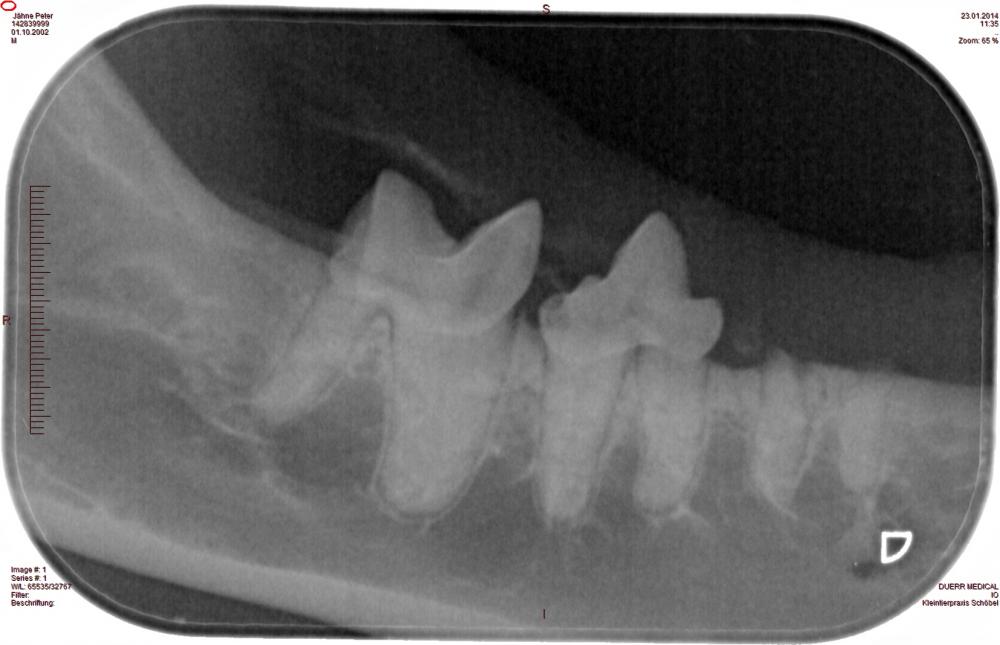

Dentalröntgen

Um Wurzelläsionen, Kiefervereiterungen und die Vitalität einzelner Zähne beurteilen zu können, ist es manchmal nötig, mit hochauflösenden Zahnfolien strahlungsarme Röntgenaufnahmen der zu beurteilenden Kieferbereiche zu machen. So können gesund wirkende, aber wurzelkranke Zähne identifiziert und behandelt werden. Aber auch überflüssige Zahnextraktionen bei Schmelzdefekten oder Verfärbungen ohne Wurzelschaden können vermieden werden.